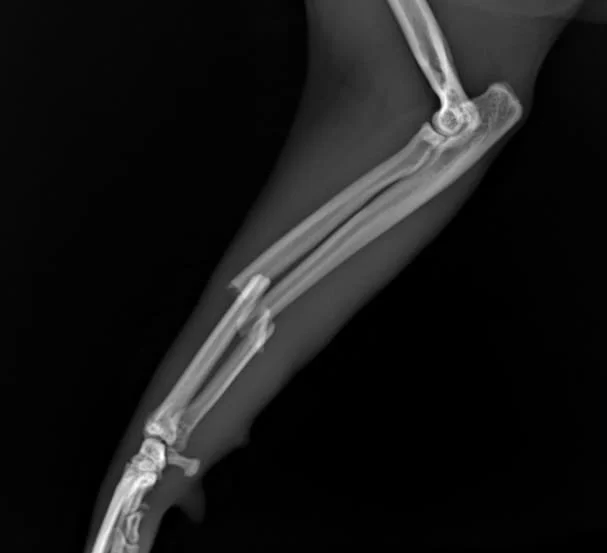

Radiographic exam reveal complete closed trasverse

mid-diaphyseal radius fracture and short oblique

mid-disphyseal ulnar fracture with small lateral butterfly fragment, with caudo-medial displacement.